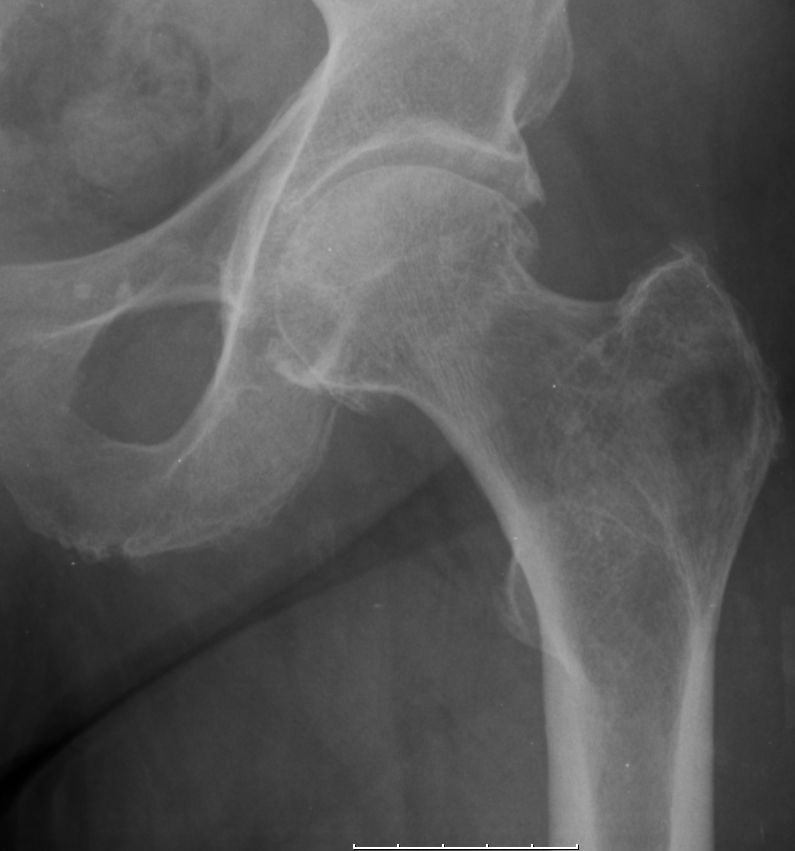

Trochanter major |

77jährige Frau mit Coxarthrose und schwerer LWS-Skoliose. 5 Monate nach diesem Bild wurde am linken Trochanter major eine 45mm große Knochenmetastase eines bis dahin unbekannten Primärtumors entfernt. | ||||||||||

![]() |

![]() | ||||||||||